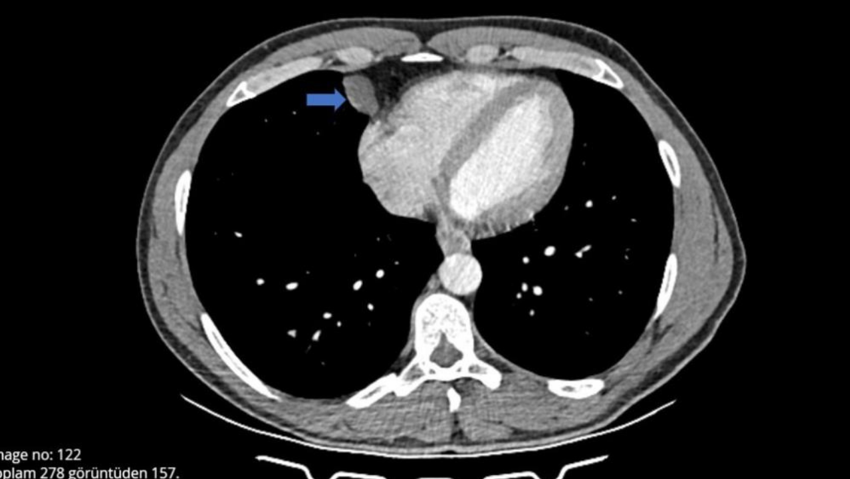

Yat kaptanlığı yapan 45 yaşındaki Ömer Can, çıktığı uzun seyahat sonrası omuzunda ağrı hissetti, öksürük ve hapşırma krizleri geçirince grip olduğunu düşündü. Can, nefes almakta güçlük yaşayınca Şanlıurfa'nın Akçakale ilçesinde hastane aciline başvurdu. Burada tomografisi çekilen Can'ın, akciğer ile kalbinin arasında bir kist olabileceği belirtildi. Can, çevresindekilerin tavsiyesi üzerine detaylı araştırma ve inceleme için, Antalya Eğitim ve Araştırma Hastanesine başvurdu. Gerekli tetkikleri yapılan Ömer Can'ın, belirtilen bölgesinde yaklaşık 2 santimlik bir kist olduğu tespit edildi ve hemen ameliyata alındı. Göğüs Cerrahi bölümünde Video Yardımlı Torakoskopik Cerrahi (VATS) yöntemiyle gerçekleşen ameliyat yaklaşık 10 dakika sürdü. Hastanede ilk kez tüpsüz olarak gerçekleştirilen ameliyat sonrası Ömer Can sağlığına kavuştu, 1 gün sonrası ise taburcu edildi.

Antalya Eğitim ve Araştırma Hastanesi Göğüs Cerrahi Kliniği Eğitim Sorumlusu Doç. Dr. Muharrem Özkaya, hastanın çekilen tomografisinde, akciğerin altında, kalbin yanında perikardiyal kisti bulunduğunu ve VATS yöntemiyle iki delikten girerek kisti aldıklarını anlattı. Normalde bu tarz ameliyatlarda göğüs tüpü kullanıldığını aktaran Özkaya, “Hastanın en büyük sıkıntısı bu tüpten dolayı. Şiddetli ağrıları olur ve taburculuğu uzar. Biz göğüs tüpü takmadan ameliyattan çıktık, operasyon 10 dakika sürdü ve bugün taburcu etmeyi planlıyoruz” dedi.